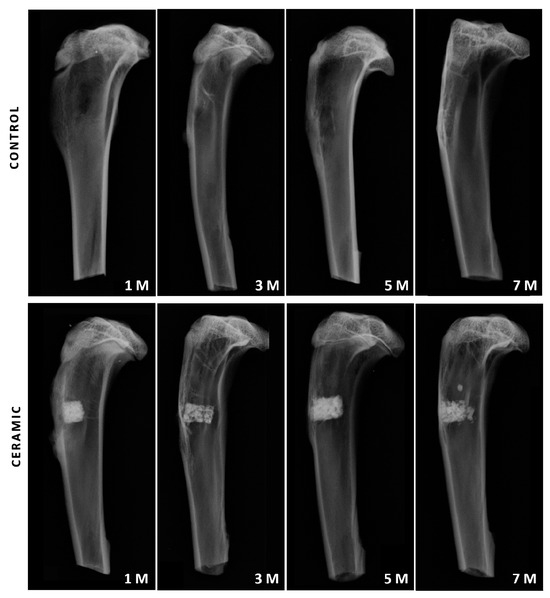

3.2. Conventional Radiological Study